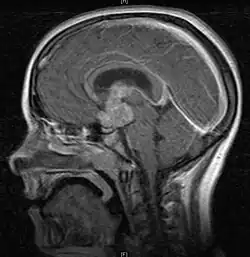

• Mainly located in midline structures, suprasellar region or pineal gland, also basal ganglia and hypothalamus

Location